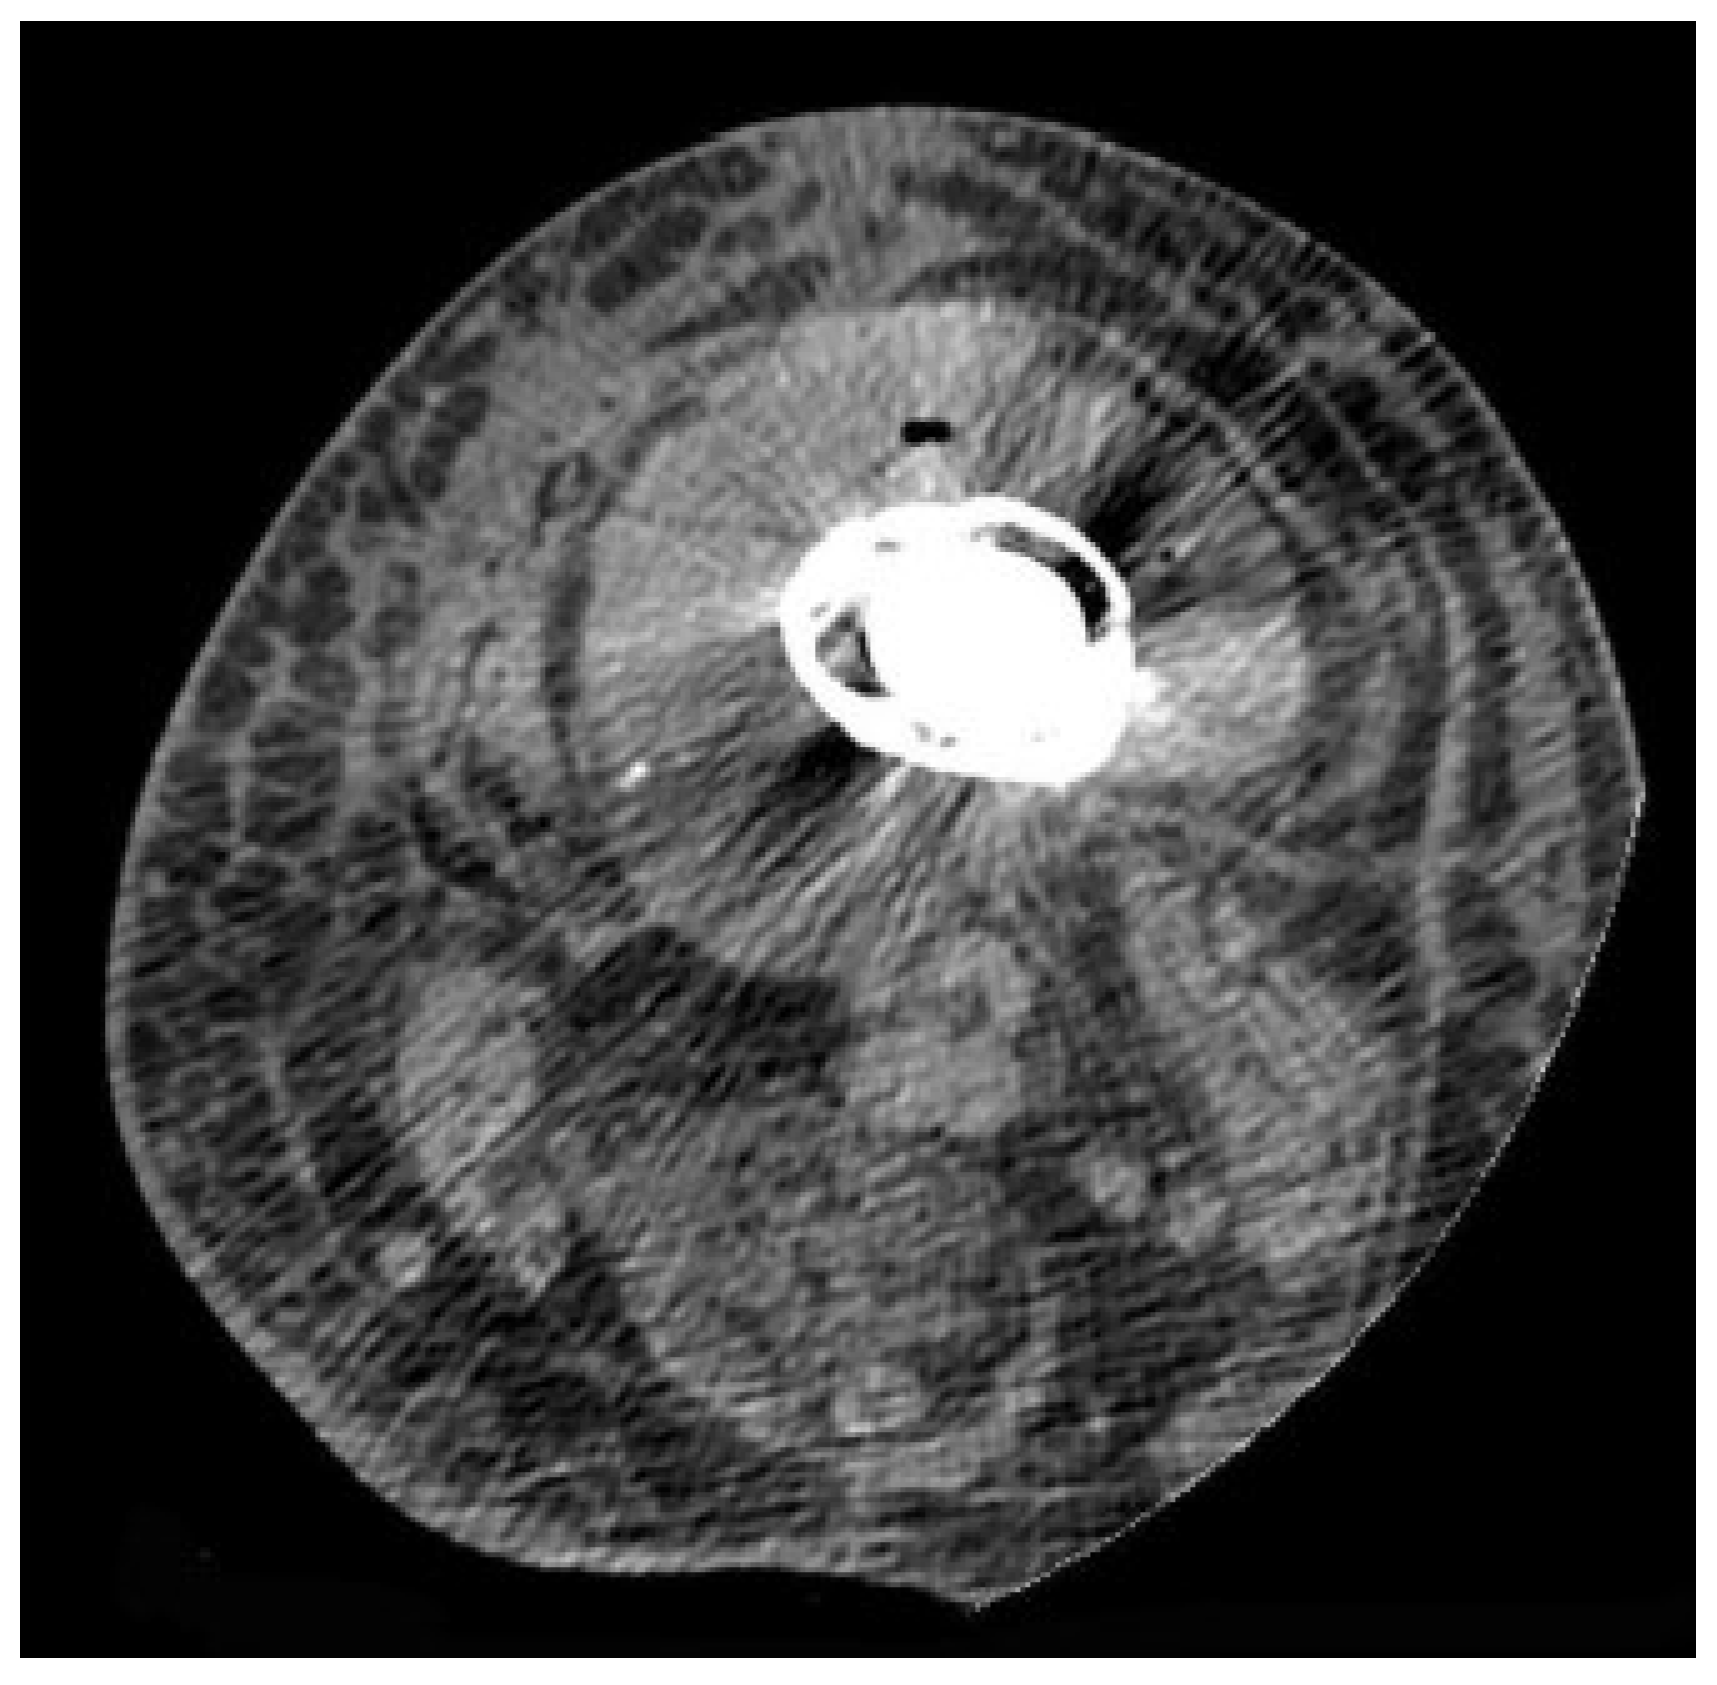

4.3. Computed Tomography

- Jacquier, A.; Champsaur, P.; Vidal, V.; Stein, A.; Monnet, O.; Drancourt, M.; Argenson, J.N.; Raoult, D.; Moulin, G.; Bartoli, J.M. [CT evaluation of total HIP prosthesis infection]. J. Radiol. 2004, 85, 2005–2012. [Google Scholar] [CrossRef] [PubMed]

- Cyteval, C.; Hamm, V.; Sarrabère, M.P.; Lopez, F.M.; Maury, P.; Taourel, P. Painful infection at the site of hip prosthesis: CT imaging. Radiology 2002, 224, 477–483. [Google Scholar] [CrossRef]

- Isern-Kebschull, J.; Tomas, X.; García-Díez, A.I.; Morata, L.; Ríos, J.; Soriano, A. Accuracy of computed tomography–guided joint aspiration and computed tomography findings for prediction of infected hip prosthesis. J. Arthroplast. 2019, 34, 1776–1782. [Google Scholar] [CrossRef] [PubMed]

| Spain | 96/H | M and C | CT-guided joint aspiration | NA | NA | NA | NA | 86.5 | [67] |

| France | 65/H | At least one soft tissue abnormality was used as an infection criterion | CT | 100 | 87 | NA | NA | 89 | [64] |

| France | 65/H | Joint distention as an infection criterion | CT | 83 | 96 | NA | NA | 94 | [64] |